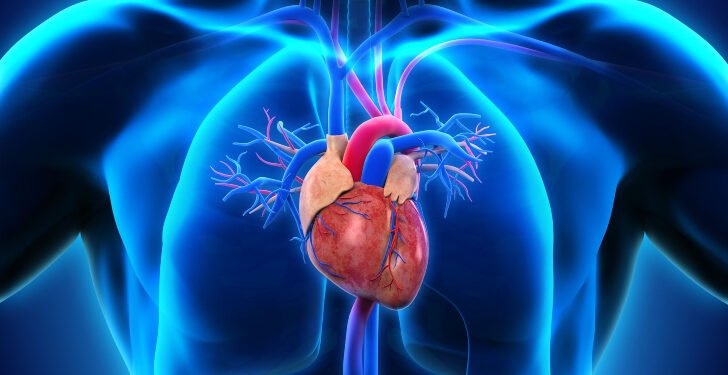

Which of these is true about your heart?

It is a muscle

Your heart is a pump. It’s a muscular organ located slightly left of center in your chest. A lot of the time, people metaphorically think that it contains your emotions, but it doesn’t.

How big is an adult heart that is usually healthy?

The size of a closed fist

The size of a closed fist

Your age, body size, and heart health can all affect how big your heart is. The heart can enlarge as a result of some diseases.

The term ______ refers to one-way “doors” that maintain blood flow in the proper direction.

Valves

The aortic, tricuspid, pulmonary, and mitral valves are the four valves that open and close in time with your heart’s pumping action. Only one direction of blood flow is necessary for your heart to function correctly. That is made possible by the “in” and “out” valves in your heart, which have flaps to seal or open the valve.

Your heart is divided into how many chambers?

4

The right and left atria are the heart’s upper chambers. The heart also has two lower chambers (the right and left ventricles). The left side of your heart receives oxygen-rich blood from the lungs and sends it through the aorta to the rest of your body. The right side of your heart pumps oxygen-poor blood to your lungs.

Through _______, blood travels from the lungs back to the heart.

Pulmonary veins

The pulmonary veins carry blood from your lungs that is rich in oxygen to your heart.